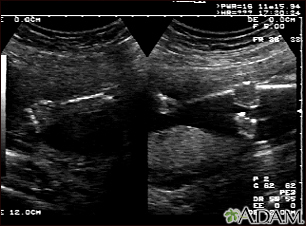

BACK TOTOP Browse A-ZSearchBrowse A-ZABCDEFGHIJKLMNOPQRSTUVWXYZ0-9 Ultrasound, normal fetus - arms and legsBackUltrasound, normal fetus - arms and legsThis is a normal fetal ultrasound performed at 19 weeks gestation. This is the type of spilt-screen display you might see during an ultrasound, or if the technician prints a copy of the ultrasound for you. This ultrasound shows both the left arm (seen in the left side of the display), and the lower extremities (seen in the right side of the display). The white areas of the arm or legs is developing bone. E-mail FormEmail ResultsName:Email address:Recipients Name:Recipients address:Message: Review Date: 10/15/2024 Reviewed By: John D. Jacobson, MD, Professor Emeritus, Department of Obstetrics and Gynecology, Loma Linda University School of Medicine, Loma Linda, CA. Also reviewed by David C. Dugdale, MD, Medical Director, Brenda Conaway, Editorial Director, and the A.D.A.M. Editorial team. The information provided herein should not be used during any medical emergency or for the diagnosis or treatment of any medical condition. A licensed medical professional should be consulted for diagnosis and treatment of any and all medical conditions. Links to other sites are provided for information only -- they do not constitute endorsements of those other sites. No warranty of any kind, either expressed or implied, is made as to the accuracy, reliability, timeliness, or correctness of any translations made by a third-party service of the information provided herein into any other language. © 1997- A.D.A.M., a business unit of Ebix, Inc. Any duplication or distribution of the information contained herein is strictly prohibited. © 1997- All rights reserved. A.D.A.M. content is best viewed in IE9 or above, Firefox and Google Chrome browser.Content is best viewed in IE9 or above, Firefox and Google Chrome browser.